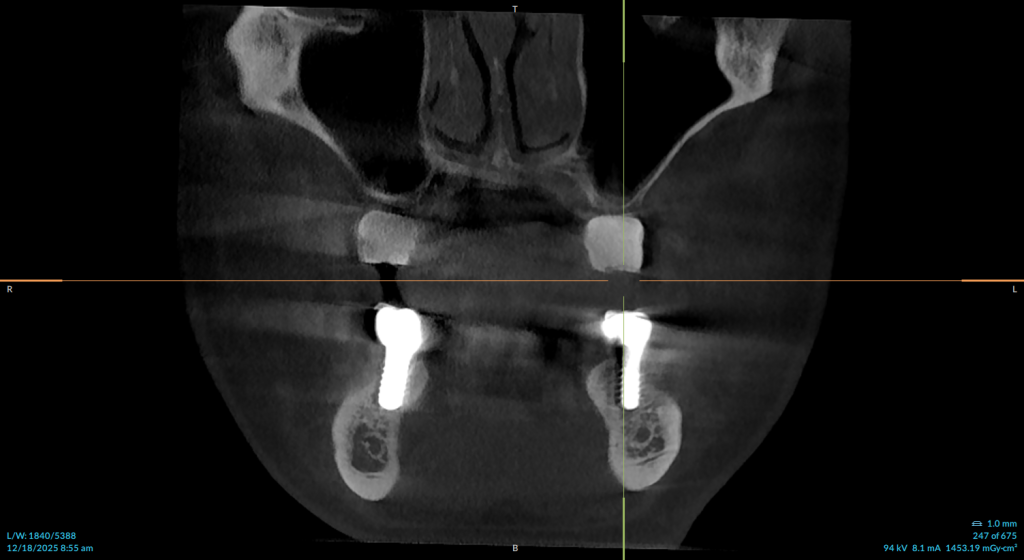

Indirect Sinus Lift: Before & After

Before